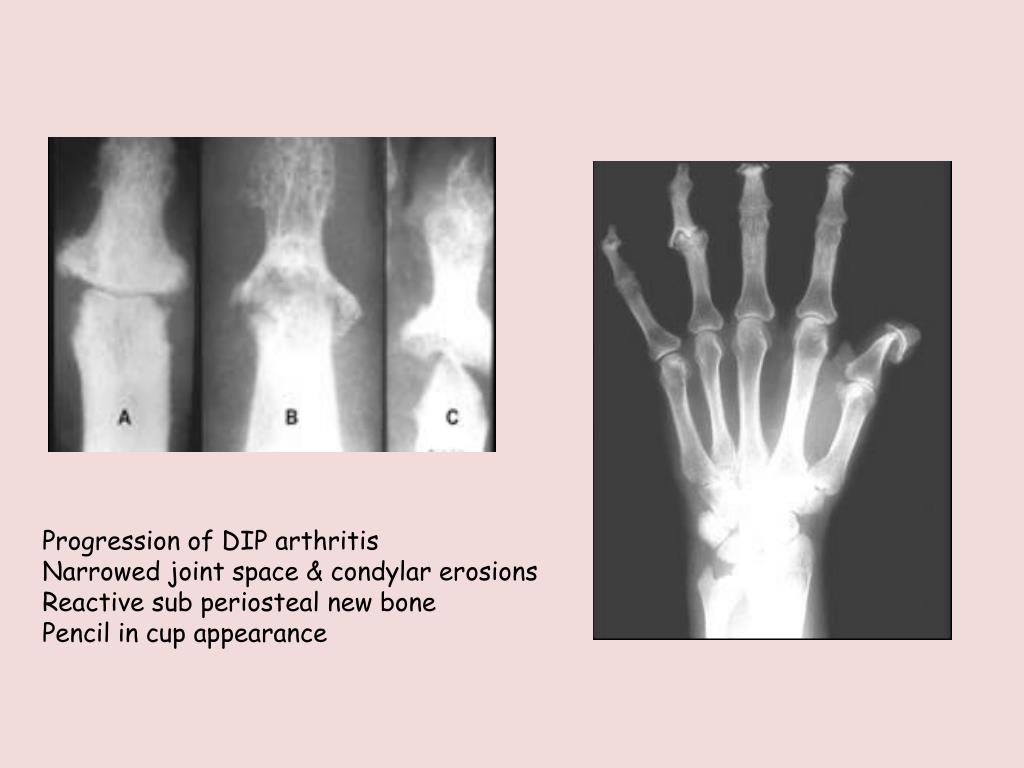

Psoriatic arthritis DIP erosions Radiology at St. Vincent's Dip Arthritis Causes The distal interphalangeal (dip) joint is actually the most common location on the body for osteoarthritis (oa). The lumps grow on the joint closest to the tip of your finger, called the distal interphalangeal, or dip joint. Diagnosis is made radiographically with. We investigated the relationship between distal interphalangeal (dip) joint involvement and disease activity in 10,038. Osteoarthritis often affects. Dip Arthritis Causes.